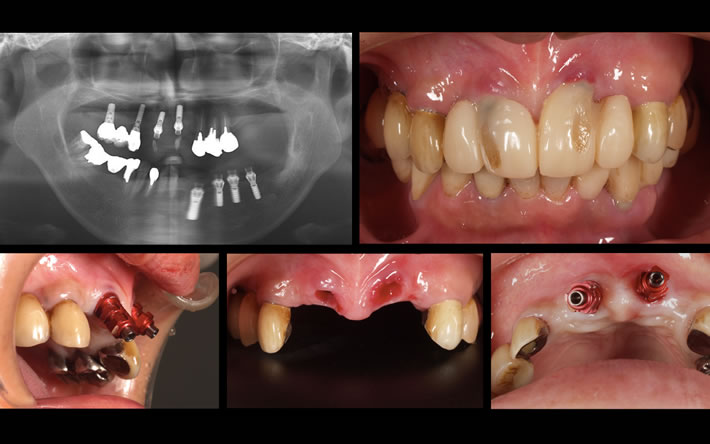

あてずっぽうに骨のある位置にインプラントを埋入してしまうと、下の写真のような見た目の問題を引き起こすだけでなく、歯肉も常に炎症をお越し、インプラント周囲炎にもつながります。 下の写真は、他医院でインプラント周囲炎を起こして転院して来られた方の症例です。インプラントの埋入位置・角度ともに無計画で、それをごまかすために作られた被せ物が、見た目にも極めて不自然です。この状態からリカバリーするには、インプラントを撤去した上で、失った骨を再生をさせるなど、多くの時間と費用がかかってしまいます。

また、正面から見れば一見普通に見える下の写真も、インプラントの埋入位置が悪いためそれをごまかす為に普通では考えられない上部構造の形にせざるを得ないという問題が発生しています。これでは下の前歯と噛み合わないため、前歯で噛み切るという動作は不可能です。